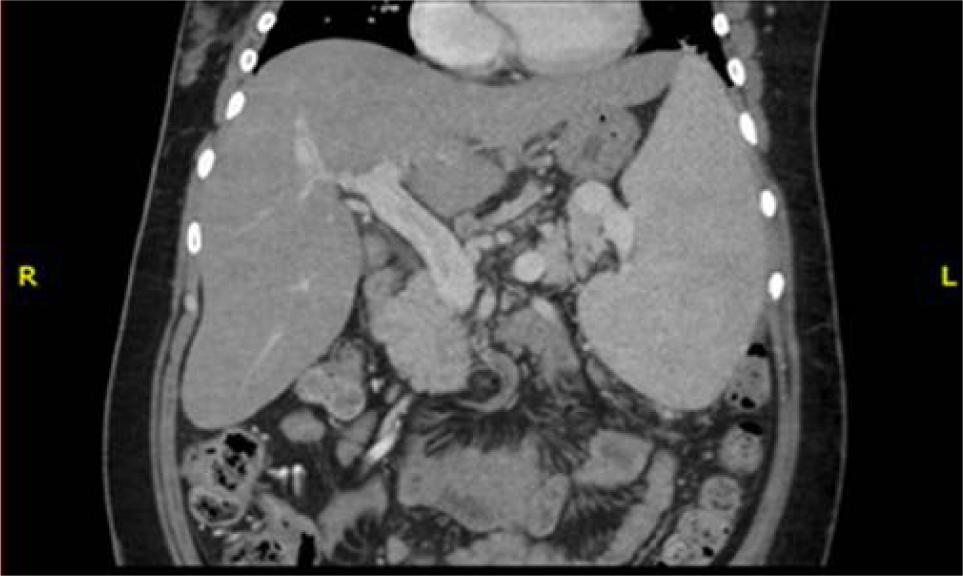

A month later, the patient presented to our medical unit with coffee ground vomiting and a recent episode of melena. His vital signs included blood pressure of 90/50 mmHg, heart rate of 92 beats per minute, respiratory rate of 20 breaths per minute, and temperature of 38.5°C. Physical examination revealed abdominal tenderness upon deep palpation of the epigastrium. Laboratory studies showed glucose 69 mg/dL, sodium 146 mEq/L, chloride 112 mEq/L, hemoglobin 9.6 g/dL, platelets 33,000 cells/mm3, neutrophils 3700 cells/mm3, total bilirubin 1.26 mg/dL, direct bilirubin 0.53 mg/dL, indirect bilirubin 0.73 mg/dL, AST 18 U/L, ALT 18 U/L, LDH 146 U/L, and C-reactive protein at 11 mg/dL. An upper endoscopy revealed large esophageal varices (Baveno VII) with signs of recent bleeding, for which it was necessary to perform variceal ligation and use terlipressin. The patient developed fever during hospitalization, and a chest X-ray indicated an alveolar pattern suggestive of infection. Antibiotic therapy with piperacillin-tazobactam was initiated, followed by meropenem and vancomycin due to the lack of improvement. The patient’s condition deteriorated further, with worsening general status, dyspnea at rest, heart rate exceeding 110 beats per minute, and right hypochondrial abdominal pain associated with hepatomegaly. Abdominal angiotomography revealed mesenteric vein ectasia, chronic thrombosis of some branches, portal hypertension, hepatic steatosis, and hepatosplenomegaly (Figure 2).

Figure 2: Abdominal angiotomography in coronal plane highlighting splenomegaly and hepatomegaly despite the diagnosis of cirrhosis.